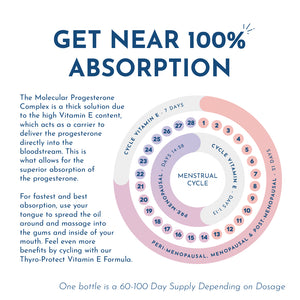

FOR PERIMENOPAUSE, MENOPAUSE, & POST-MENOPAUSE:Start with 3 drops 5x per day for 2 to 4 weeks.

Then continue with 3 drops 3x per day. Should be cycled 3 weeks on, then 1 week off. The dosage can be increased as necessary.

FOR PMS/PRE-MENOPAUSE: 3 drops 1-3x per day on days 14 through 28 of your menstrual cycle.

Dosage (3 drops) can be repeated as needed for more severe symptoms. The dosage can be increased as necessary.

FOR HOT FLASHES: Start with 5 drops 5x daily and increase as needed until hot flashes resolve. Should be cycled 3 weeks on, then 1 week off. If hot flashes return during the week off, then reduce progesterone break to a minimum of 3 days.

*Note: For best results and highest absorption, use your tongue to spread the oil around and massage into the gums and inside your mouth. The Molecular Progesterone Complex is a thick solution due to the high Vitamin E content, which acts as a carrier to deliver the progesterone directly into the bloodstream. This is what allows for the superior absorption of the progesterone compared to alternative products.